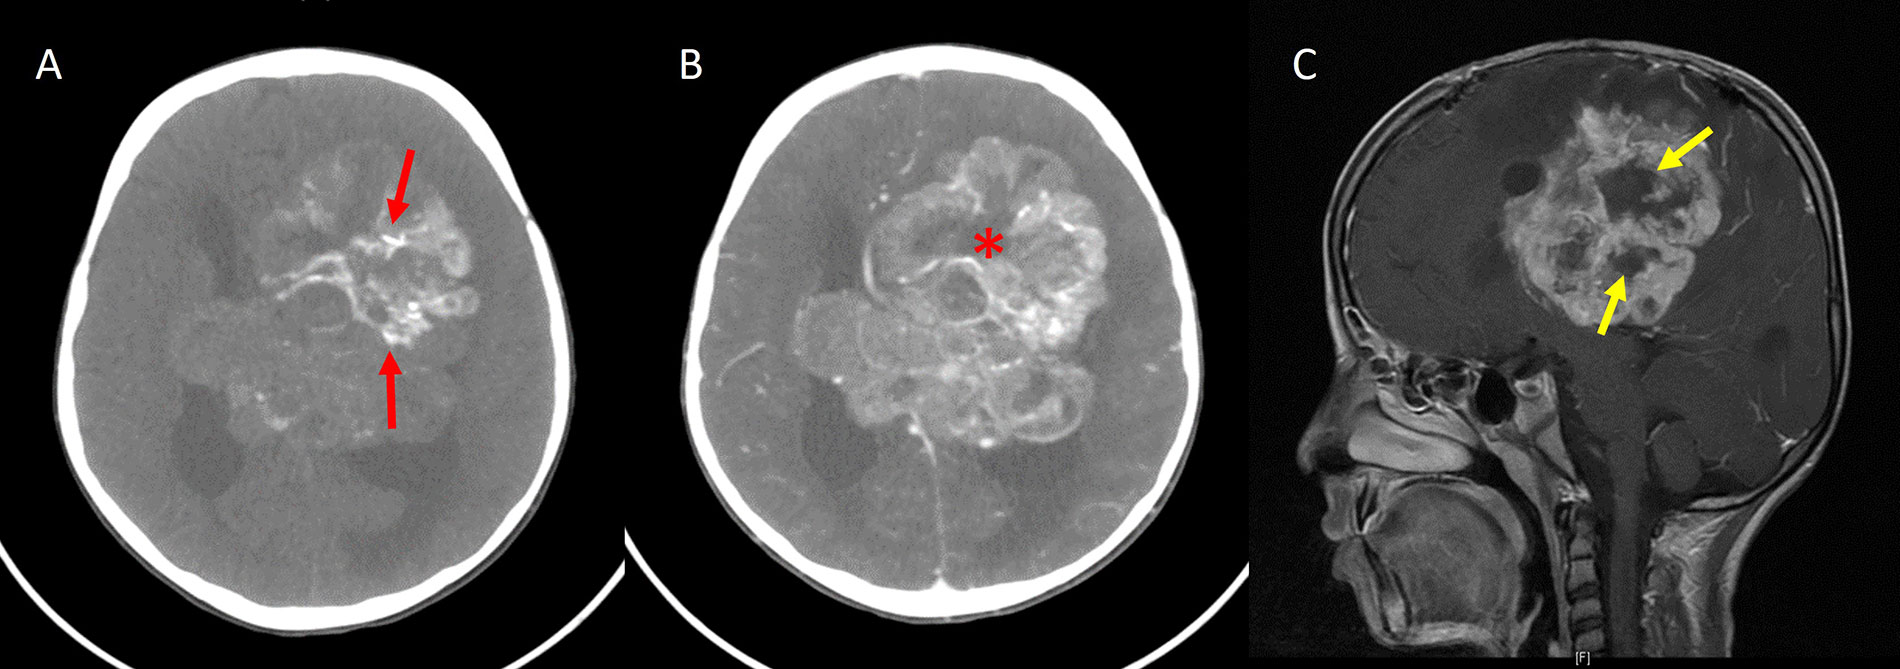

Periwinkle sign. A. Axial noncontrast-enhanced CT image shows a large heterogeneous mass in the periventricular location of the left frontoparietal lobe with centripetal calcification (red arrows); B. axial contrast-enhanced CT image showing heterogeneous enhancement of the lesion with the central necrotic area (asterisk), resembling the shape of a flower; C. sagittal contrast-enhanced T1W image of the same patient also shows a central non-enhancing area of necrosis in the shape of a flower (yellow arrows)

Blooming was seen in 20 cases on susceptibility-weighted MR imaging, out of which 13 cases had CT imaging, and all showed calcification on CT. The “periwinkle sign”, i.e. the flower-like appearance of the tumor with the central area of necrosis and centripetal calcification [25], was observed in 17 (68%) cases. Another pattern of calcification resembling a spoke wheel was observed in these cases, which has been termed the “stellate sign”. The periwinkle sign on MRI and CT is demonstrated in Figures 4, 5, and 6. A significant association was found between the periwinkle/stellate sign and the periventricular location (n = 13, 86.7%, P value = 0.045). It was observed less frequently in the intraventricular location (n = 2, 50%), and purely cortical location (n = 1, 33%).